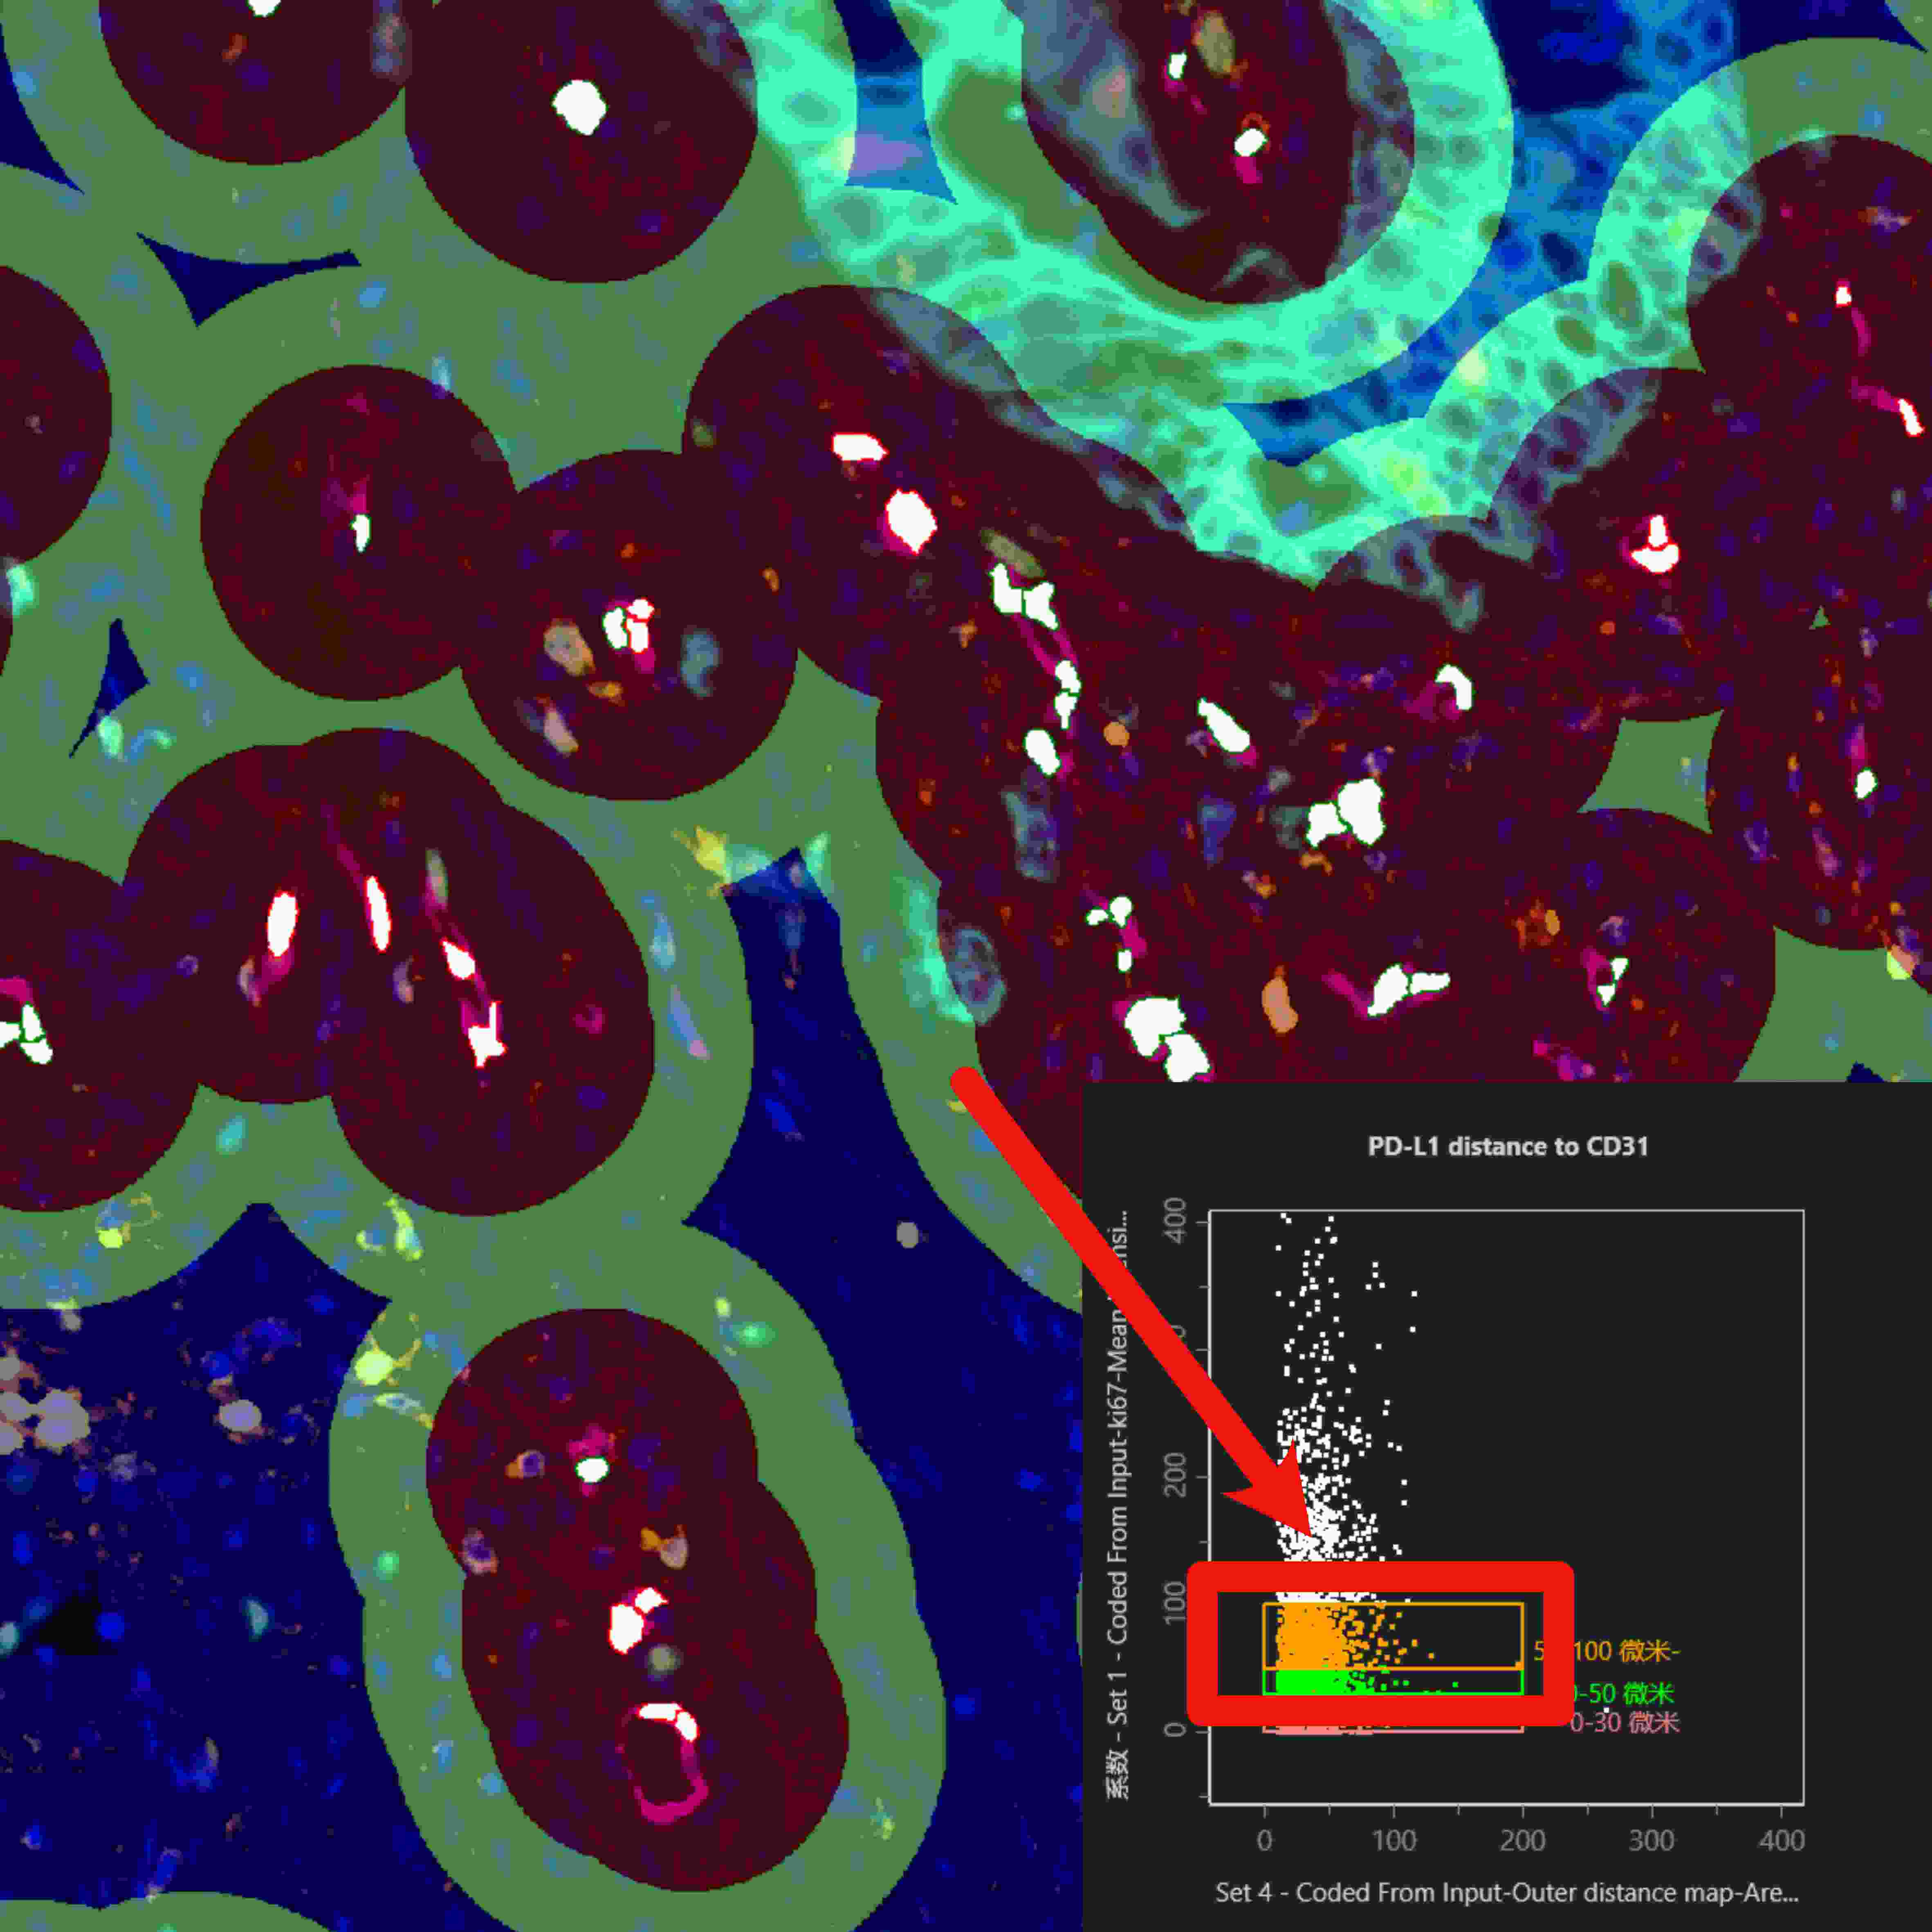

在单细胞表型分析与组织识别分析的基础上,利用StrataQuest可进一步分析不同细胞与不同组织类型间的空间分析关系。

除上述一站式完整解决方案外,TissueGnostics 还能助力研究人员开展更深入的实验方法研究,通过定制化染色扫描分析服务获取更丰富的分析数据。例如,在组织切片染色扫描环节,可依据实验方案实现 50 种以上荧光标记的多轮循环染色扫描;后续分析中,还能生成空间水平的细胞间连线图、组织周围特定距离细胞分布图等多元化结果。